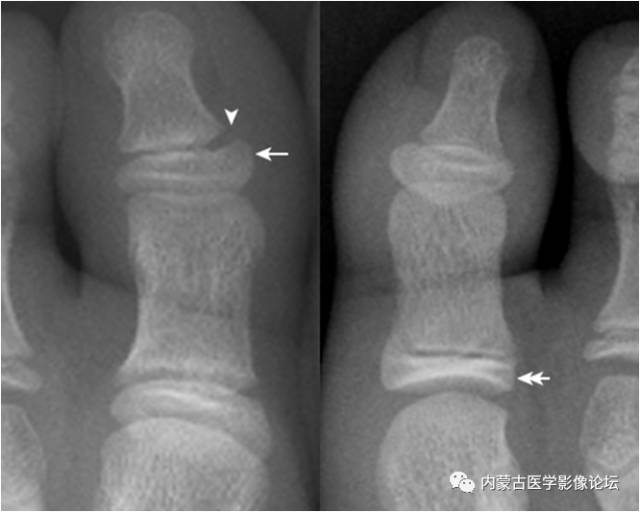

19.拇趾多分籽骨:拇趾内外侧籽骨可表现为二分籽骨(箭)或三分籽骨(箭头),为正常变异,需与籽骨骨折、坏死鉴别。骨折边缘多不规则,坏死密度多不均。

22.趾骨骨骺:拇趾远节趾骨骨骺内侧较外侧宽(箭),其与趾骨干骺端间距离较宽(箭头),为正常表现,勿误认为是骺离骨折。近节趾骨骨骺可呈扁平状,并密度增高,亦为正常表现,勿误认为坏死。